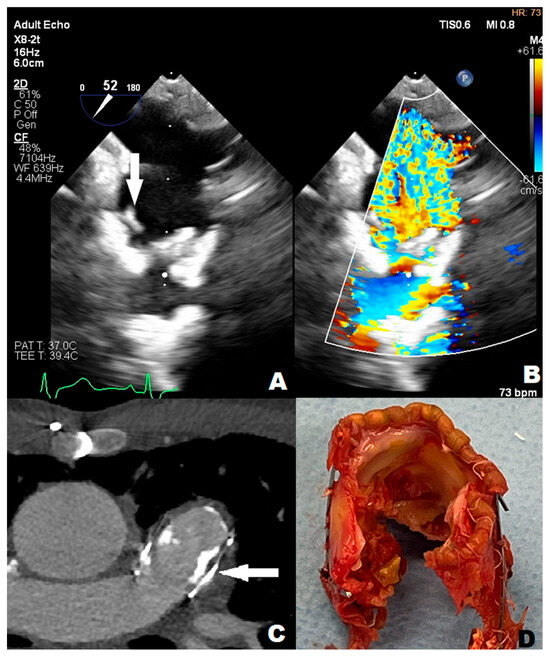

3.1. Case 1